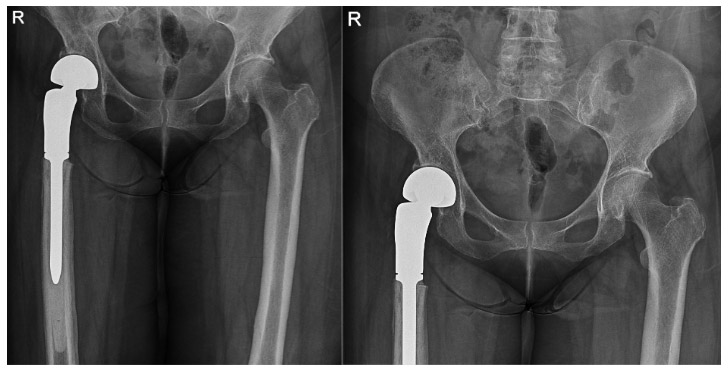

Postoperative: The procedure involves removing the tumorous portion of the bone and implanting a cemented tumor prosthesis.